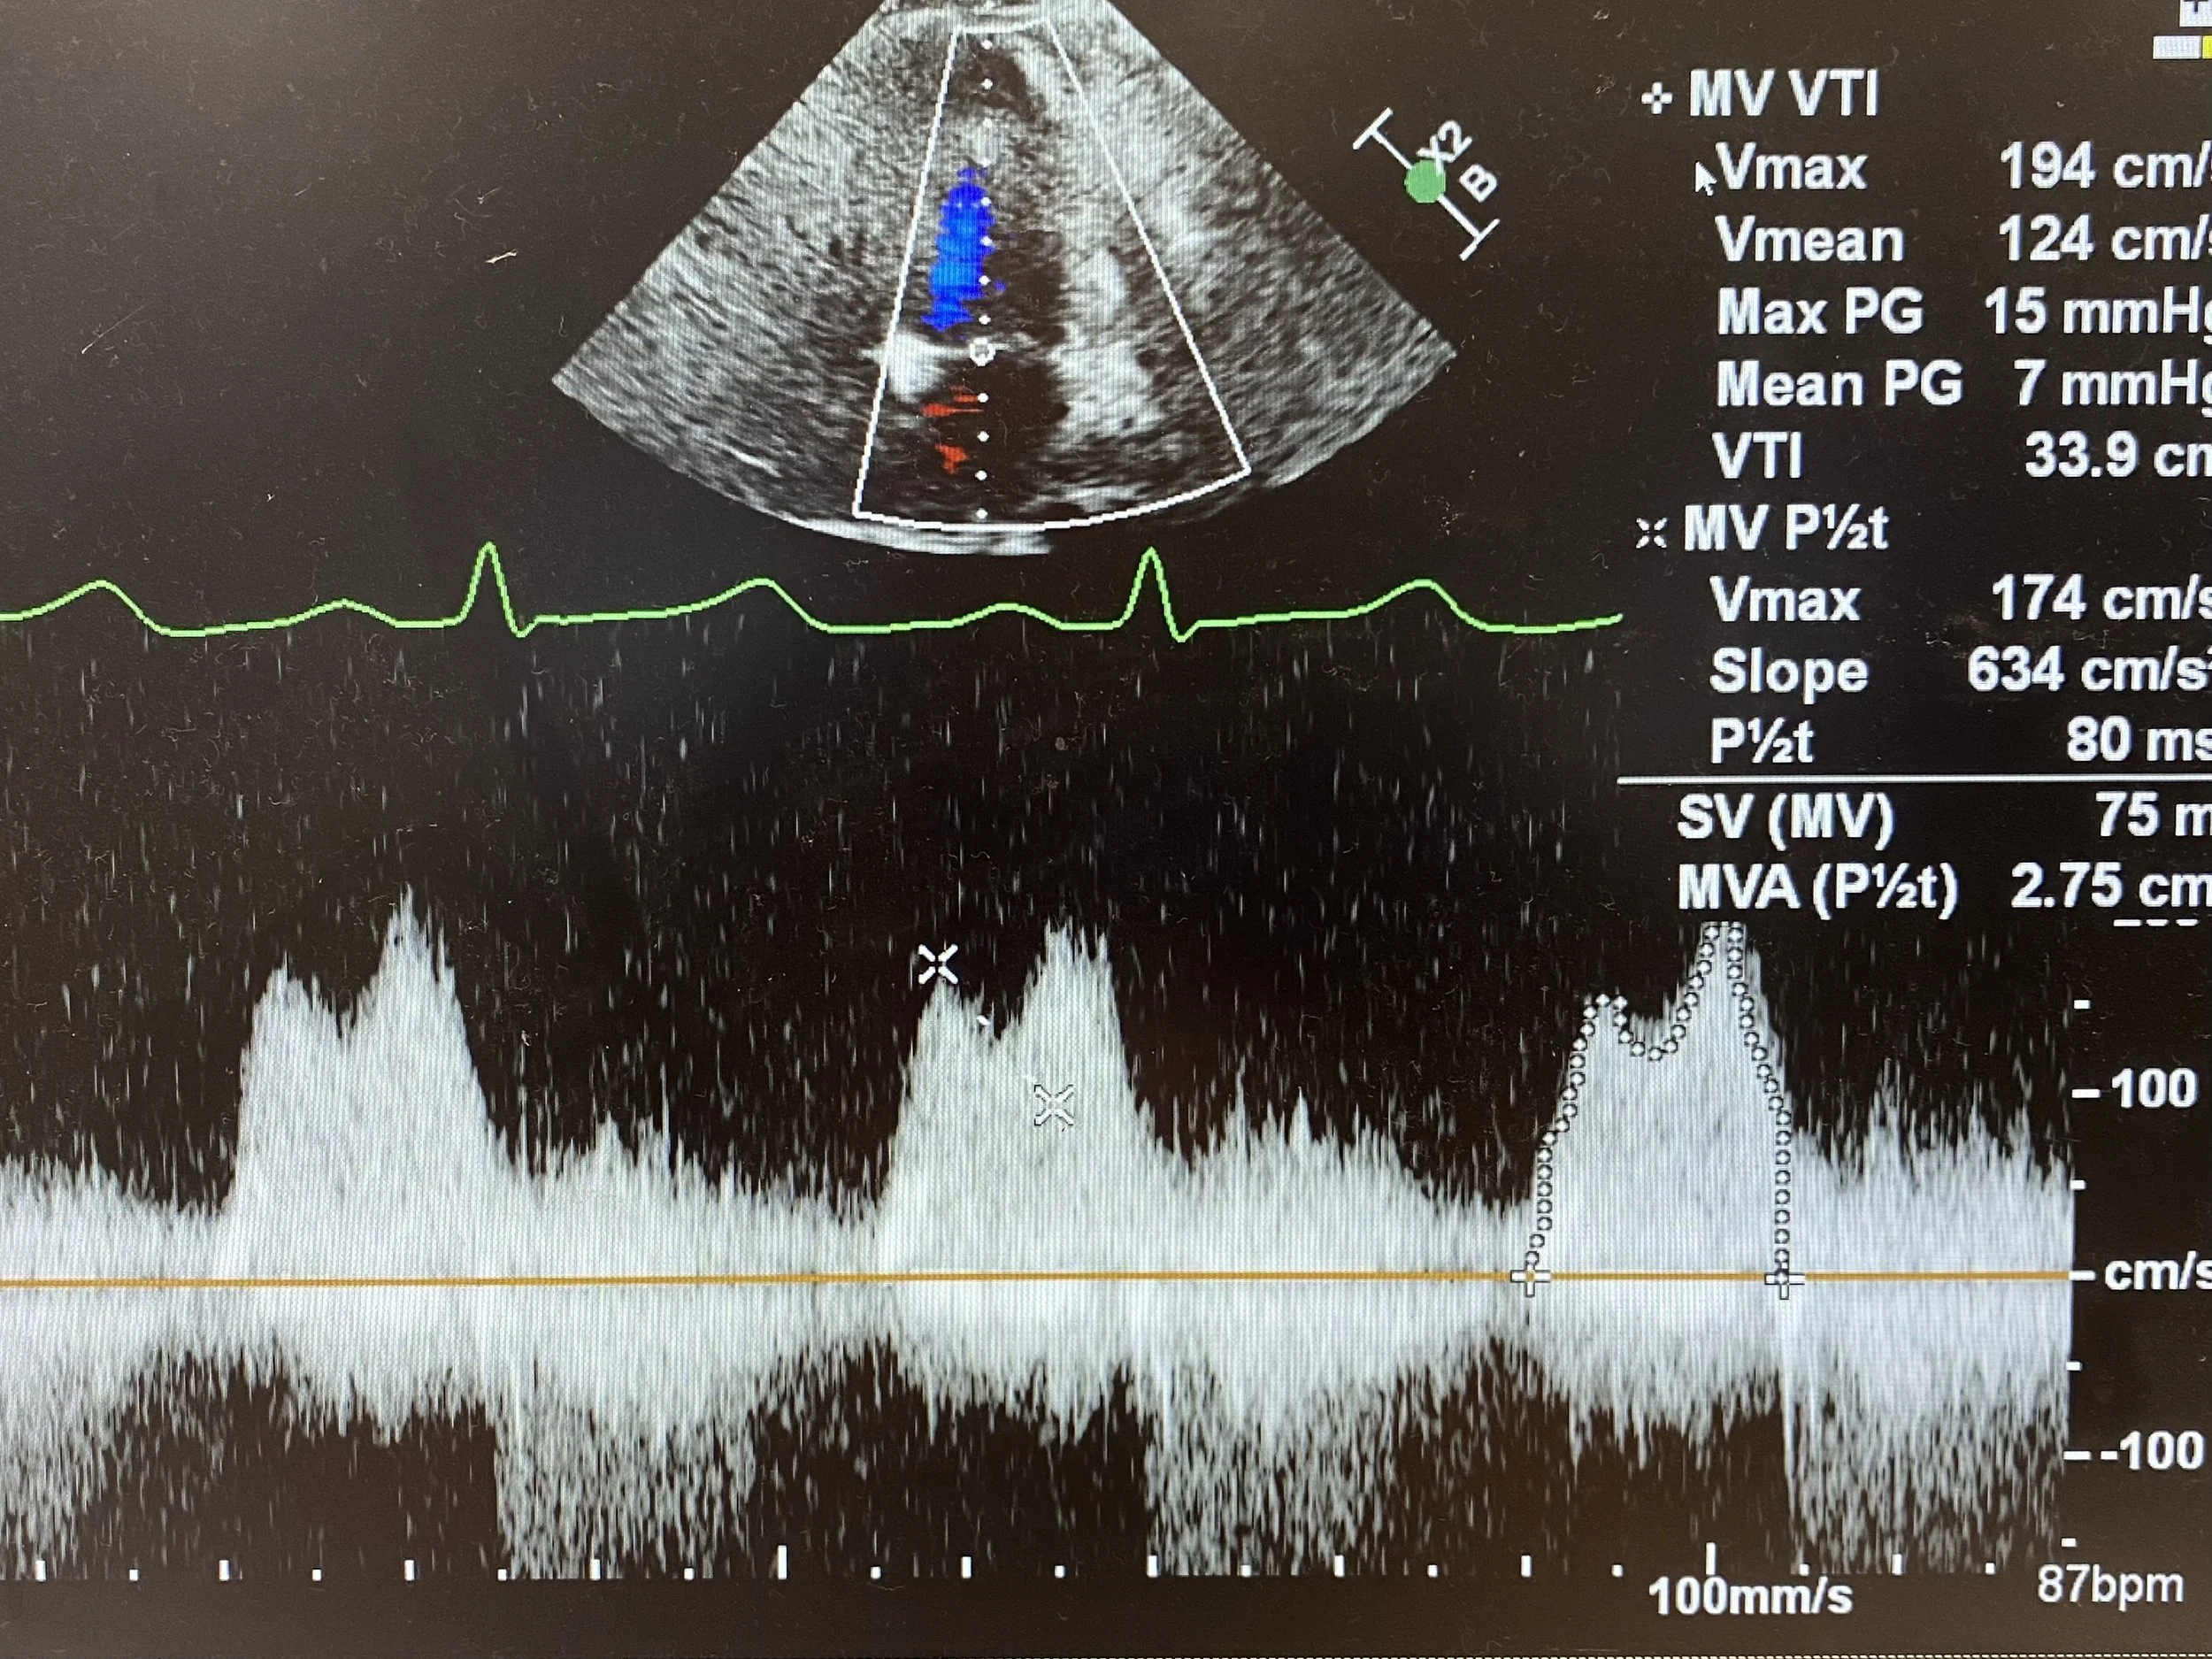

2 — Assess Mitral Valve Doppler

This is best achieved by putting CW doppler through the mitral valve from an Apical 4-Chamber view to get a saddle-shaped trace such as the one below. The first peak is the E-wave (diastolic filling), and the second peak is the A-wave (atrial kick).

The VTI is measured by tracing around the entire E-A curve during diastole (see dotted line on third complex). This will then calculate a Mean Peak Gradient (in this case VTI is 33.9cm and the Mean PG is 7mmHg). As a rough rule:

• Mild to moderate mitral stenosis has a Mean PG 5-10mmHg

• Severe mitral stenosis has a Mean PG greater than 10mmHg

* However the gradient will increase as heart rate increases, so always reference the Mean PG to the heart rate at time of study.

The Pressure Half-Time is a measure of the gradient of the deceleration slope immediately after the E-wave. If mitral stenosis is SEVERE, the pressures will start to equalise more slowly (as there only a small orifice through which blood can flow to equalise the pressure) and thus the slope will be less steep. Conversely, if MS is only MILD (and the valve area is relatively large) pressures can equalise quickly and the slope will be steep.

The gradient is marked here on the second complex (line between the two crosses) and the machine calculates the time for this pressure to half (in milliseconds). Here, the P1/2t is 80ms. As a guide:

• Mild mitral stenosis P1/2t is around 100ms

• Moderate mitral stenosis P1/2t is around 200ms

• Severe mitral stenosis P1/2t is around 300ms

So in this case, the Mean PG is around 7 (in the mild to moderate range) but will likely decrease as the heart rate decreases (HR at time of study was 87). And the pressure half time is 80ms. Thus both of thess measurements are in keeping with only MILD Mitral Stenosis